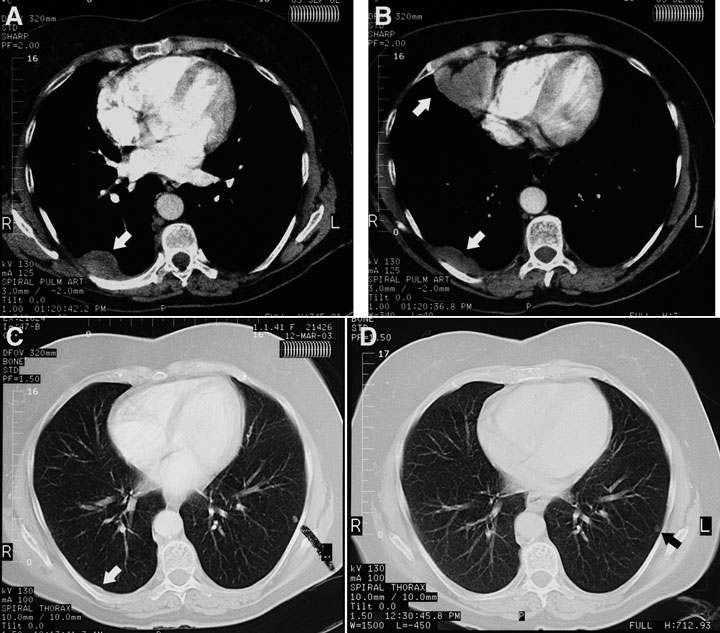

A chest radiograph taken before referral showed a pleural density measuring 10 cm × 2 cm overlying the posterior aspect of the right lower lobe, with no pleural plaques or other stigmata of asbestos exposure. A CT pulmonary angiogram performed the same day to exclude pulmonary embolism showed three pleural masses in the right side of the chest — the first corresponding to the opacity visible on the chest radiograph in the right costovertebral gutter at the level of the tracheal bifurcation, the second having a diameter of 6 cm and located in the right cardiophrenic angle (not of fatty attenuation), and the third in the right posteromedial costophrenic recess, just above the diaphragm (Box 1A and Box 1B). The lungs, mediastinum and upper abdomen (including the pancreas and para-aortic nodes) were normal.